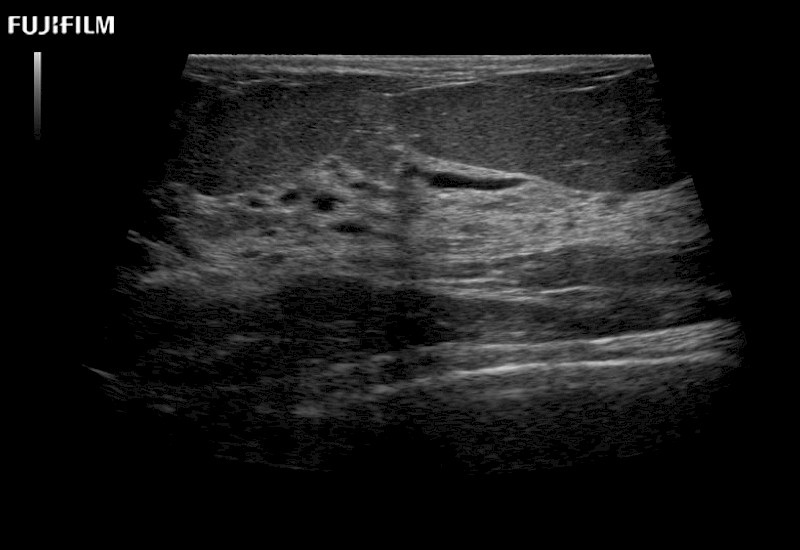

Curved array deep penetration “T” style finger-grip transducer for open surgical procedures.